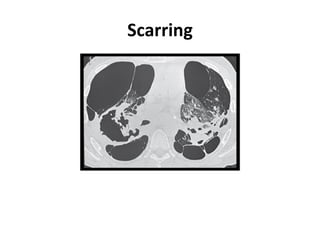

Scarring

Typical CT ofsarcoidosis CT scan features of Sarcoidosis

• 14.